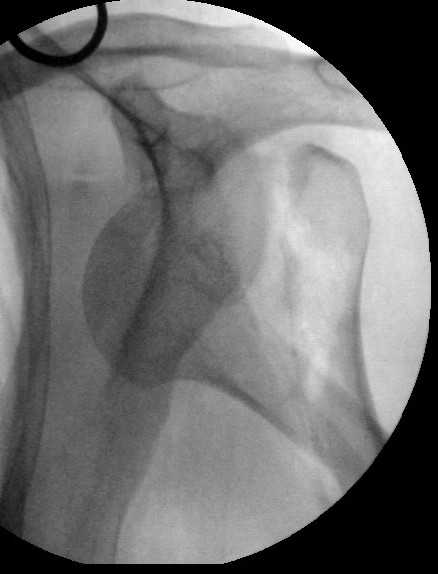

Попытка закрыто изменить положение не удалась. Передним доступом сделали открытую репозицию, гленоид без особенностей. Временно фиксировали спицами и остроконечным костедержателем. Фиксировали гвоздем T2 PHN (Stryker). Для профилактики вывихов после введения проксимальных винтов ротировали дистальный отдел кнаружи на 30

градусов как аналог остеотомии по Weber. Снимки в приложении. Комментарии и критика привествуются.

Attempt of closed reduction failed. Open reduction via anterior approach. The head was temporarily fixed by wires and sharp clamps. Fixation by a nail - T2 PHN (Stryker). The distal fragment has been rotated 30 degrees externally after proximal locking for dislocation prevention as "virtual" Weber osteotomy. Images attached.

Comments/critics are welcome.

I have never used that particular implant.

Is there only a single screw in the head?

> Is there only a single screw in the head?

All 3 screws are in the head. The feature of the nail is that it has four holes oriented not 45 degrees to frontal or sagittal planr, but anatomically to the head and both tubercles. The holes in the nail are threaded so angular stability is perfect, and contain a nylon bushing

preventing any screw rotation/back out.